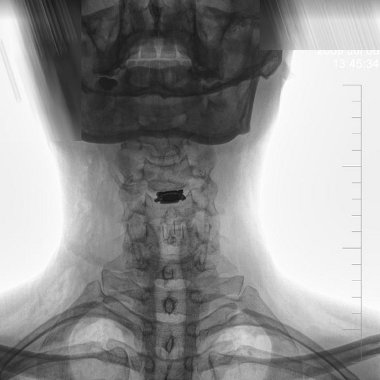

Moja oferta obejmuje między innymi zabiegi wykonywane w zakresie kręgosłupa. Przeprowadzam operacje dyskopatii lędźwiowej, piersiowej i szyjnej w technice mikroskopowej. W czasie pracy stosuję najnowsze techniki w chirurgii kręgosłupa szyjnego w kontroli mikroskopowej, stabilizacje i protezy trzonów, a także nieruchome implanty (cages) i ruchome dyski szyjne (TCDR).